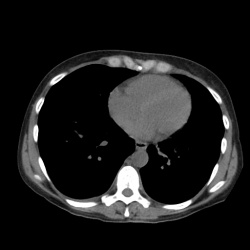

Мужчина за 60. Неприятные ощущения за грудиной. Направлен на на дообследование из ООД. Проведены эндоскопия и КТ.